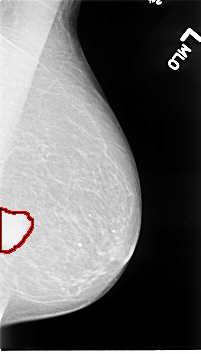

B_3066_1.LEFT_MLO

LEFT_MLO LINES 4592 PIXELS_PER_LINE 2608 BITS_PER_PIXEL 12 RESOLUTION 50 OVERLAY

FILE: B_3066_1.LEFT_MLO.OVERLAY

TOTAL_ABNORMALITIES 1

ABNORMALITY 1

LESION_TYPE MASS SHAPE IRREGULAR MARGINS CIRCUMSCRIBED-ILL_DEFINED

ASSESSMENT 4

SUBTLETY 5

PATHOLOGY MALIGNANT

TOTAL_OUTLINES 1

BOUNDARY